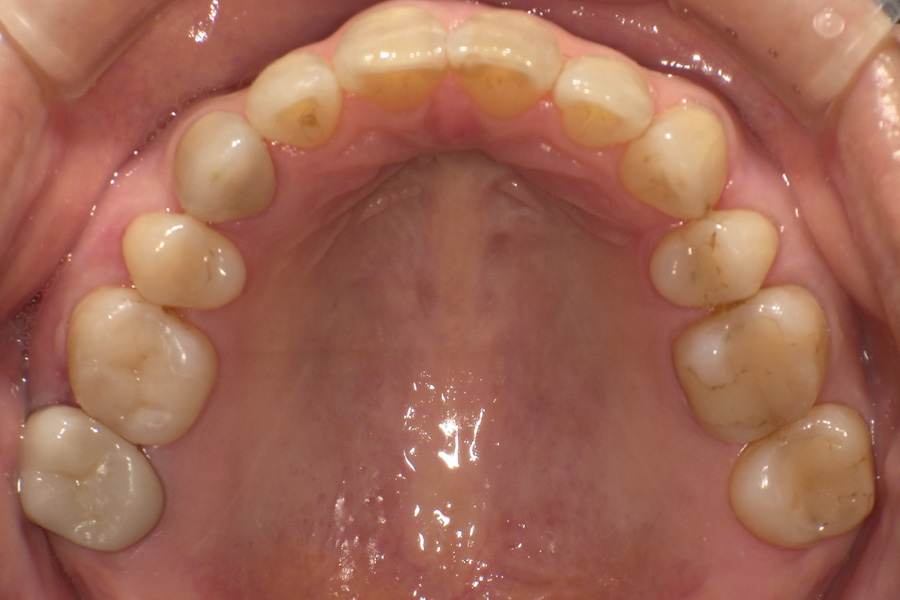

虫歯があるから削ったり悪くなったから抜くのではなく、まずは虫歯と歯周病が起きないようにより良い環境づくりをすること、そうすることによって歯を長く維持することが可能となります。

そのためには、健康状態に関する情報と生活習慣などの状況を把握したうえで、お口の中のリスク評価をおこないます。

その結果をもとに、お一人お一人にあった治療計画をご提案させていただきます。